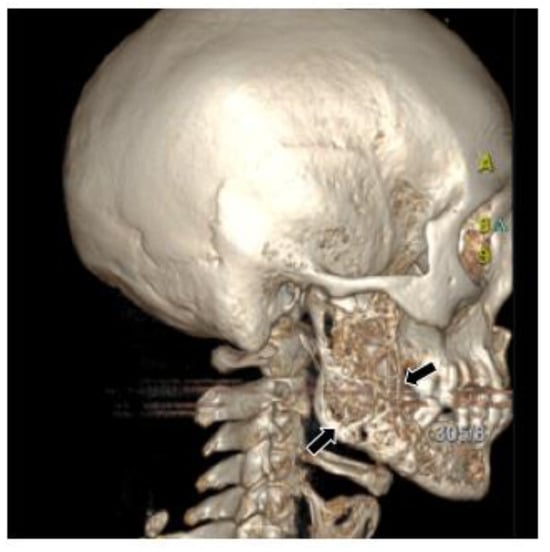

2.1. Case 1

2.2. Case 2